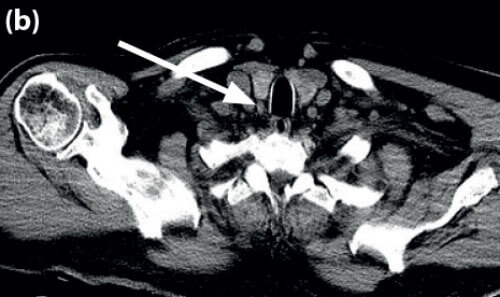

Using the PACS software, the corresponding CT images are viewed using multiplanar reconstruction (MPR). The PACS ruler is used to measure the following (see Figures 2-5).

- Size of the parathyroid gland in three dimensions.

- Distance from the cricoid to the parathyroid gland.

- Distance from posterior edge of thyroid to the parathyroid gland.

- Distance from the skin to the parathyroid gland.

Figure 4. Coronal CT image to show measurement from posterior inferior edge of thyroid gland to PT gland (5.58mm).